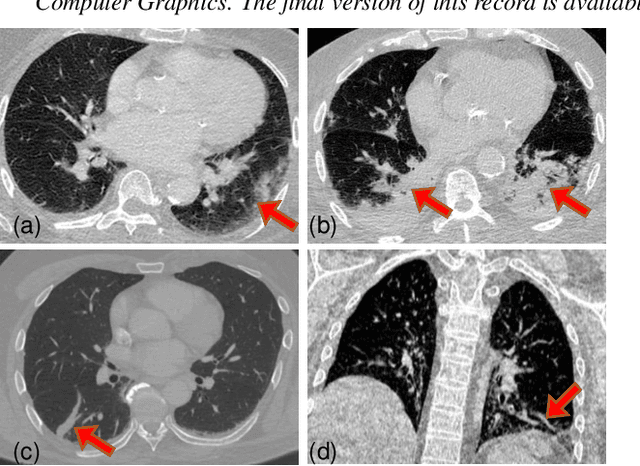

Abstract:Significant work has been done towards deep learning (DL) models for automatic lung and lesion segmentation and classification of COVID-19 on chest CT data. However, comprehensive visualization systems focused on supporting the dual visual+DL diagnosis of COVID-19 are non-existent. We present COVID-view, a visualization application specially tailored for radiologists to diagnose COVID-19 from chest CT data. The system incorporates a complete pipeline of automatic lungs segmentation, localization/ isolation of lung abnormalities, followed by visualization, visual and DL analysis, and measurement/quantification tools. Our system combines the traditional 2D workflow of radiologists with newer 2D and 3D visualization techniques with DL support for a more comprehensive diagnosis. COVID-view incorporates a novel DL model for classifying the patients into positive/negative COVID-19 cases, which acts as a reading aid for the radiologist using COVID-view and provides the attention heatmap as an explainable DL for the model output. We designed and evaluated COVID-view through suggestions, close feedback and conducting case studies of real-world patient data by expert radiologists who have substantial experience diagnosing chest CT scans for COVID-19, pulmonary embolism, and other forms of lung infections. We present requirements and task analysis for the diagnosis of COVID-19 that motivate our design choices and results in a practical system which is capable of handling real-world patient cases.